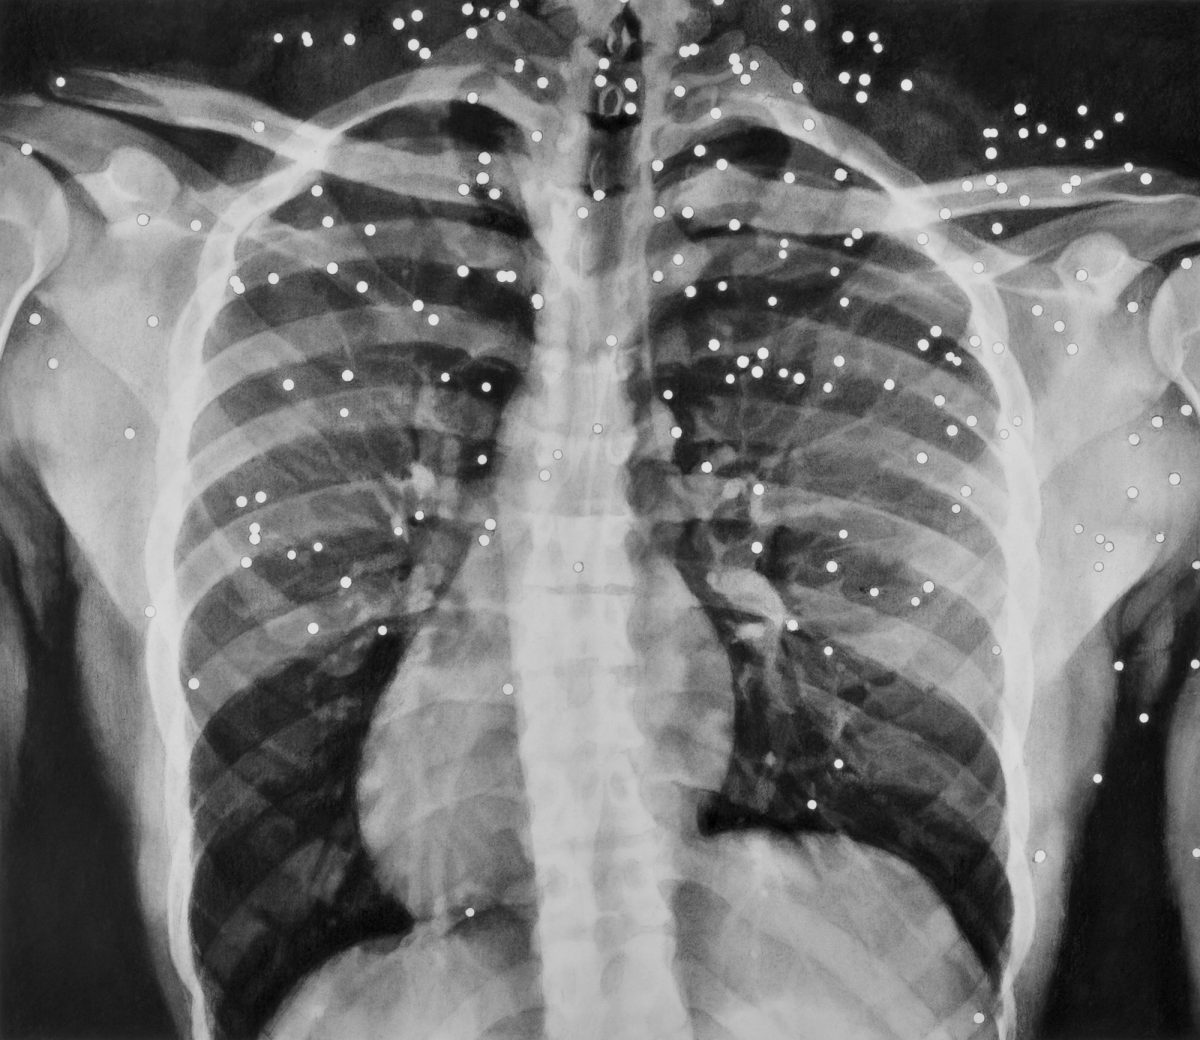

Prize awarded to: Cat.94, Steven Dixon GUNSHOT 1 (Wohl Central Hall)